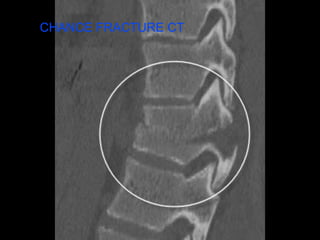

C H A N C E F R A C T U R E S

CHANCE FRACTURE CT

O F TE N A S S O C I A T E D W I T H I N T R A B D O M I N A L A N D S P I N A L I N J U R Y S E A T B E L T I N J U R Y

V E RY C O M M O N W I T H S E A T B E L T I N J U R Y C H A N C E F R A C T U R E S